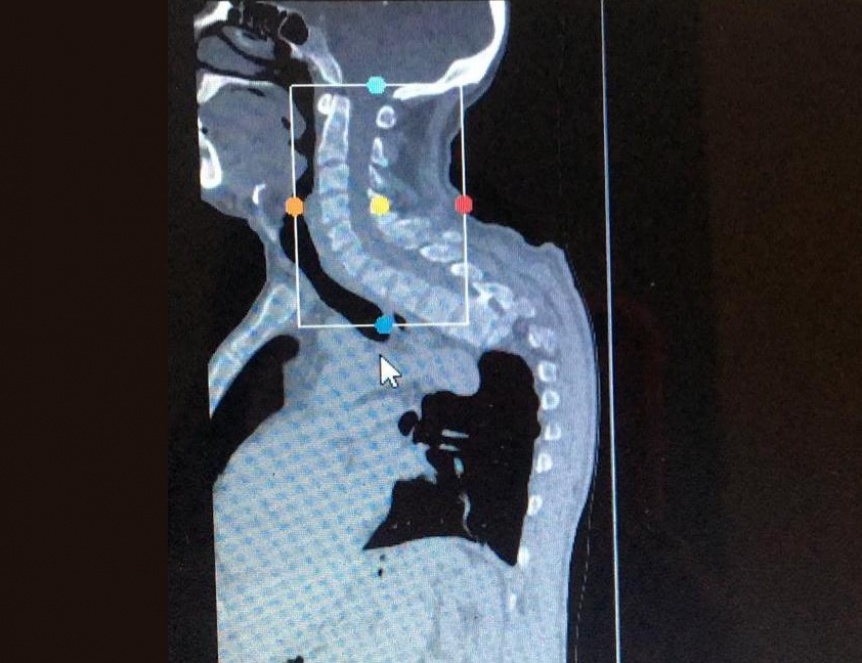

El Hospital de Alta Complejidad en Red El Cruce desarrolló en conjunto con la Universidad Nacional Arturo Jauretche (UNAJ), un biomodelo, mediante la impresión 3D, de una columna desde la vértebra C5 a T11, para un paciente que se encuentra a la espera de una cirugía.

Se trata de un hombre de 43 años de edad que presenta una deformidad cifotica dorsal con lesión medular progresiva. La deformidad cifotica dorsal es una alteración en las curvaturas normales de la columna, que puede provocar lesión medular.

Mediante un software específico, la docente procesa la imagen tomográfica de la columna del paciente, para luego enviar el archivo procesado a la impresora 3D, previamente configurando la misma para lograr a la perfección las formas y terminaciones realistas de cada una de las vértebras. Una vez impresas las vértebras, las mismas deben ser perfeccionadas manualmente y enlazadas respetando la forma de la columna del paciente.